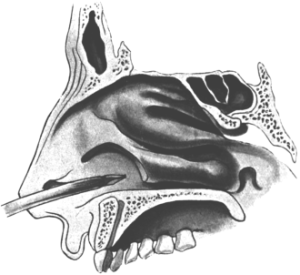

| 293. | First Step in the Removal of the Anterior End of the Middle Turbinal | 594 |

| 294. | Second Step in the Removal of the Anterior End of the Middle Turbinal | 594 |